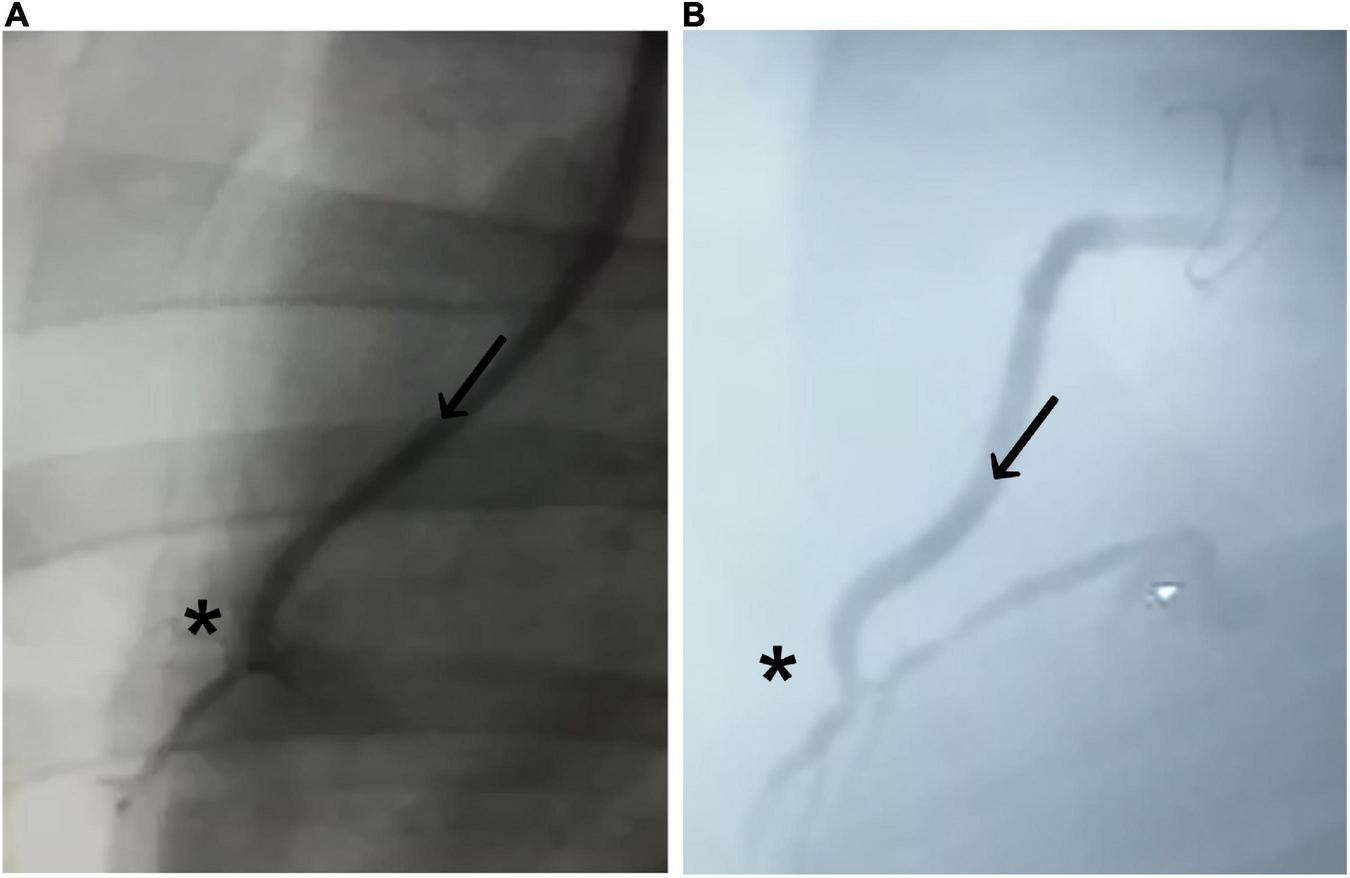

The initial postoperative angiography conducted directly after finishing the CABG procedure revealed sufficient graft patency of the implanted BC graft in all eight animals. There were no signs of graft dissection or narrowing at the distal anastomotic site (Figure 3A). All animals recovered within 24 h, consuming solid food and water 24 h after surgery.

Figure 3. Coronary angiogram of the implanted graft. (A) Immediately after implantation and (B) 4 weeks after implantation. Bacterial cellulose (BC)-vascular graft shows good postoperative results with a complete patency profile as coronary artery bypass and antegrade flow through the BC graft (arrow in direction of the flow) toward the distal anastomosis (*).

Coronary angiography 4 weeks after CABG confirmed sufficient graft patency without signs of graft dissection or burst in all animals (Figure 3B; Table 2). None of the animals showed a completely closed lumen of the graft, dissection, ruptures, or bleeding during the 4-week period when evaluated with angiography.